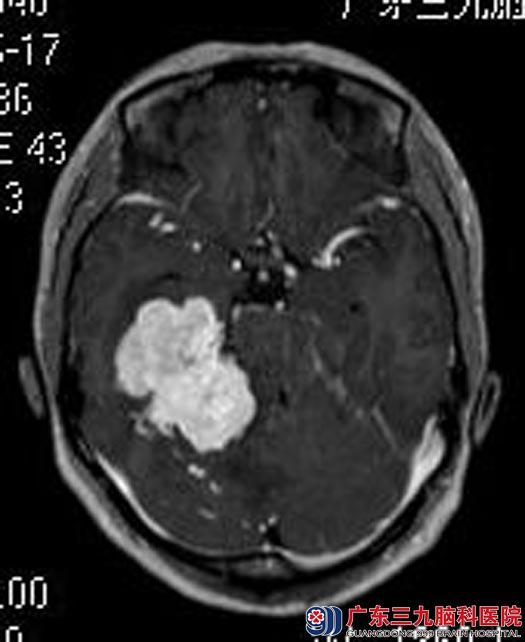

入住广东三九脑科医院综合神经外科后,复查头颅MRI提示:右侧中后颅窝跨小脑幕示一不规则团块状高信号为主占位性病变,大小约51.1mm×41.5mm×45.2mm,考虑脑膜瘤可能性大。

完善各项检查后,由鲁明主任主刀,在全麻下行右侧中后颅窝占位切除术,术中显微镜下见肿瘤质软,呈灰白色,血供丰富,超声吸引器瘤内切除部分肿瘤,肿瘤沿岩骨向后长入后颅窝,可见肿瘤内侧滑车神经、小脑幕,电磁刀切开并切除小脑幕约1cm,见颞骨岩部、斜坡肿瘤组织,肿瘤与周围关系紧密,牵拉抬起肿瘤,向下见肿瘤与滑车、三叉神经及后组神经上缘粘连,分离后予以切除。手术顺利,术后黄女士未出现神经损害症状,现已康复出院。术后病理结果:血管周细胞瘤(相当于WHO II 级)。

▲手术前

手术前